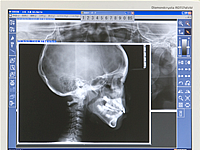

精密検査

詳しい問診・診査を行った後、顔・口の中の写真とレントゲンを撮影します。